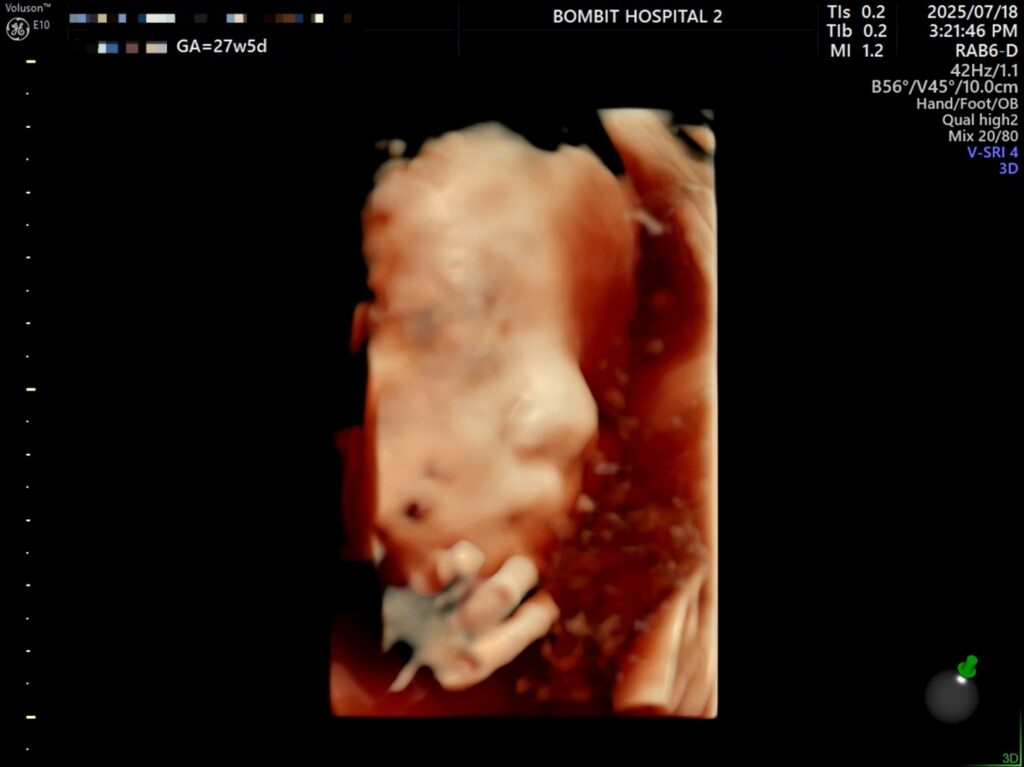

입체초음파로 본 단비는 처음에 완전히 엎드려있었다. 바닥을 향해 엎드려서 얼굴을 파묻고 귀 밖에 안 보여줌.. ㅜㅜ

초코우유도 못 먹는 몸인지라, 초음파실 샘이 권유한대로 물을 마시고 로비를 한 3바퀴정도 힘차게 걷고 나서 다시 초음파를 봤다. 단비가 여전히 엎드려있길래 선생님이 배의 특정 부분을 두드리셨는데(단비 미안).. 단비가 움직였다!

– 처음에 보여준 귀.. 귀욥

– 통통한 손가락